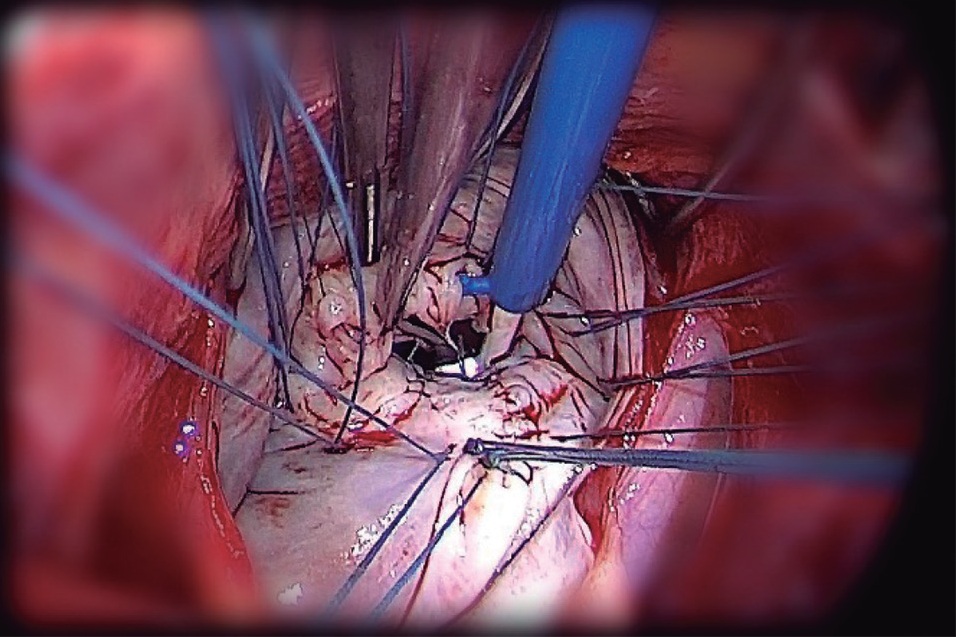

Objetivo: El propósito de este trabajo es demostrar la utilización de neocuerdas de politetrafluoroetileno expandido preformadas para la realización de una plástica mitral exitosa.

Material y métodos: Entre marzo y diciembre del 2018 se intervinieron 13 pacientes con insuficiencia mitral grave quirúrgica por enfermedad degenerativa con criterios quirúrgicos a los cuales se les implantó cuerdas nuevas preformadas para la reparación mitral en el Hospital Universitario Austral.

Resultados: Se repararon en forma exitosa la insuficiencia mitral grave a los 13 pacientes colocando neocuerdas preformadas en la valva posterior en 6 pacientes; en la valva anterior, en 4 pacientes; y, en ambas valvas, en 3 pacientes.

Conclusiones: Las neocuerdas de politetrafluoroetileno permitieron realizar la plástica reparadora de la insuficiencia mitral en forma satisfactoria, segura y reproducible para el prolapso de cualquier segmento valvular mitral.